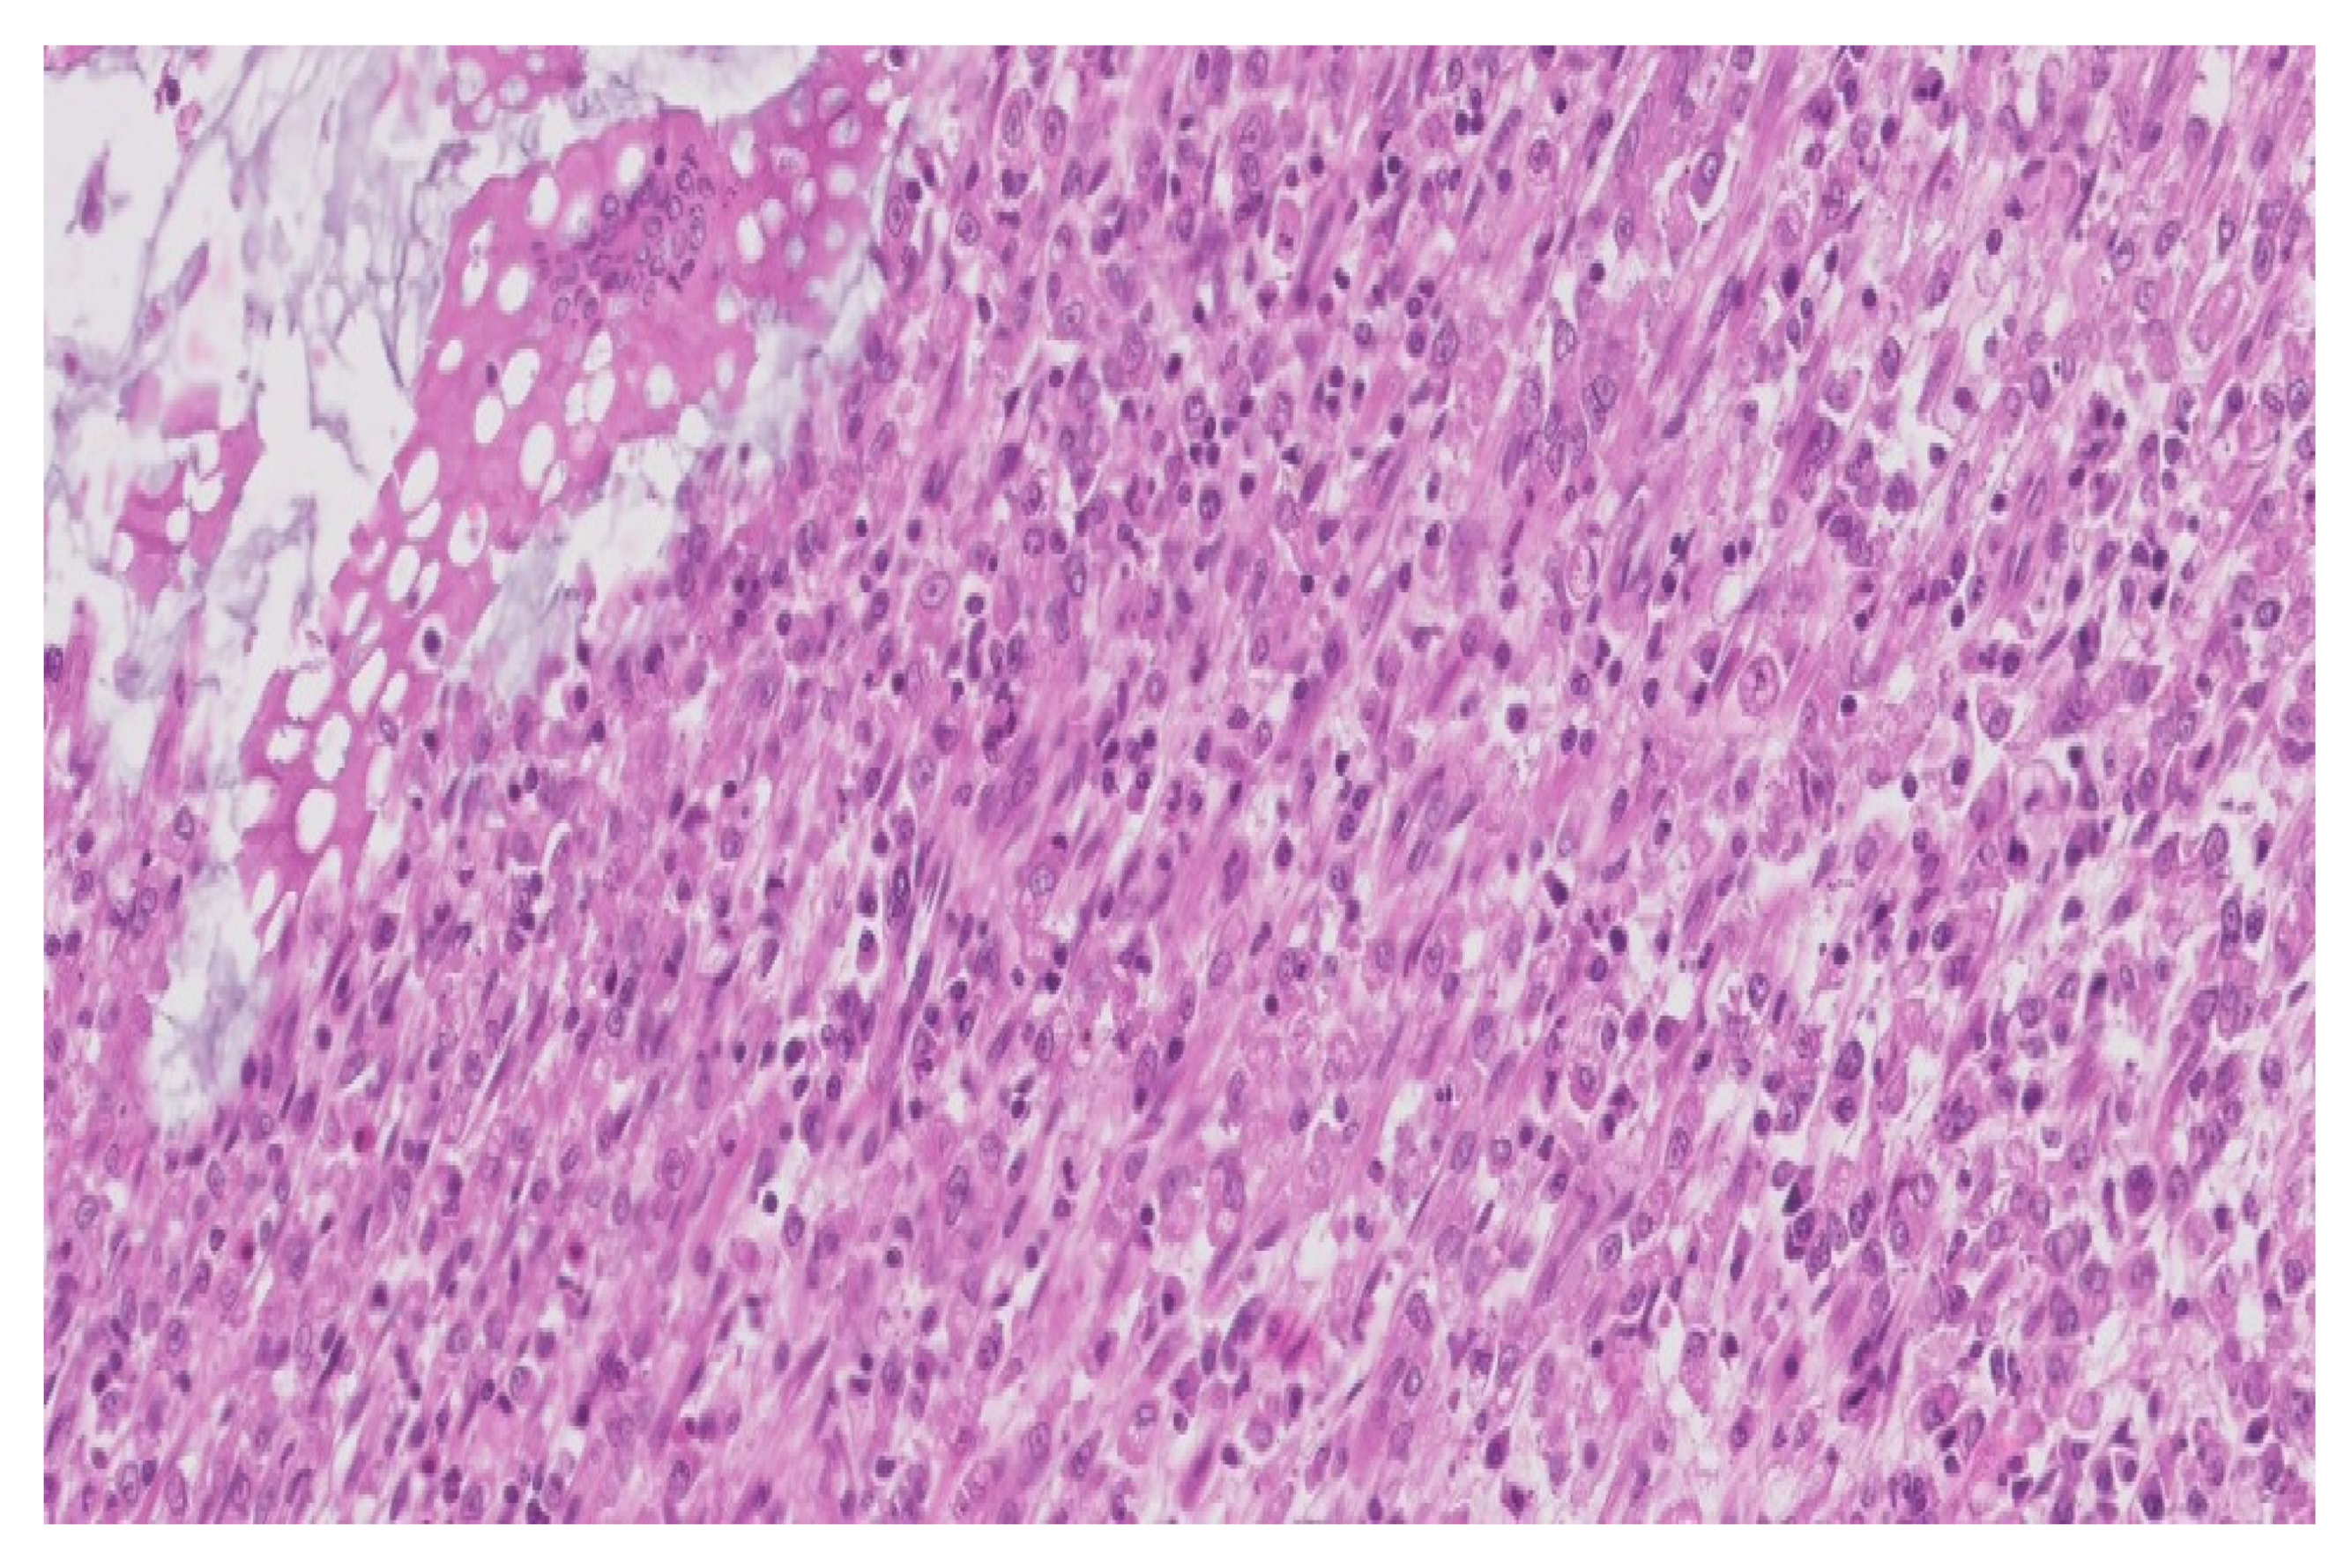

The result of the immunohistochemical tests confirmed that the inflammatory infiltrate was predominantly comprised of:

- macrophages (positive CD68)-illustrated in the Figure 4

Figure 4. Positive CD68 in the macrophage infiltrate (×200). - with rare dispersed T lymphocytes (positive CD3),

- rare B lymphocytes (alpha positive CD20, CD79) especially in the lamina propria,

- rare plasmacytes (alpha positive CD79),

- as well as rare mast cells (positive tryptase).

Additionally, most macrophages were positive for CD204 (MSR1), a receptor that plays a role in phagocytosis (Figure 5).

Alpha-SMA was positive in the smooth muscle cells, from the level of the muscularis mucosae and the own muscle, being negative in the inflammatory cells.